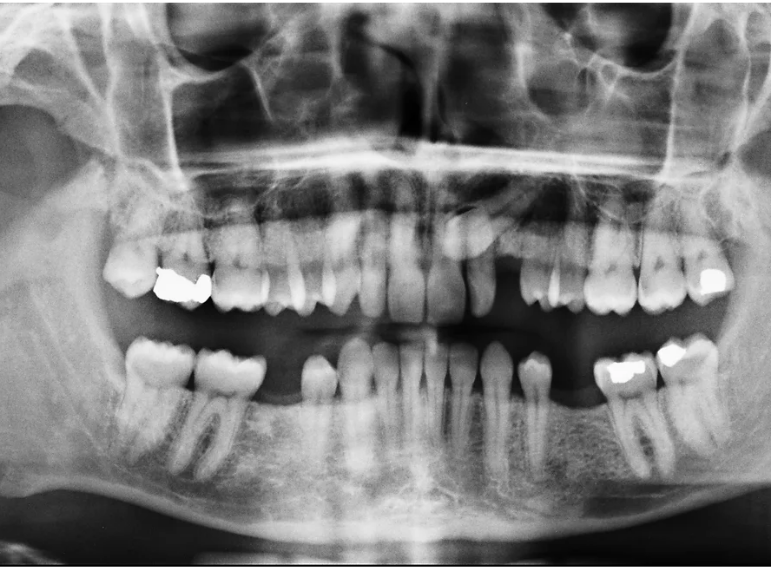

Case 9 – Implants

Placement of implants in a patient with hypodontia.